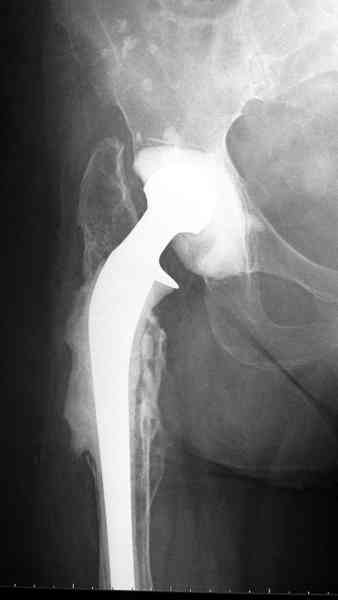

Для спейсера в бедро использовал старый длинный бедренний компонент меньшего диаметра, облепленный со всех сторон цементом с антибиотиком.

№3-6 снимки с осложнением

и последние снимки.